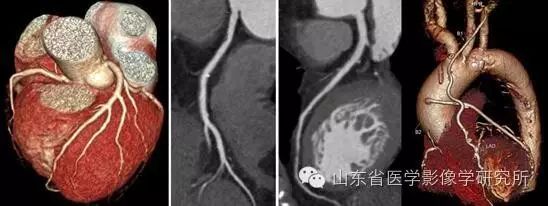

▲冠状动脉CTA联合CT心肌灌注评估冠状动脉粥样硬化斑块风险。

▲成人冠状动脉CTA成像及搭桥术后效果评估。